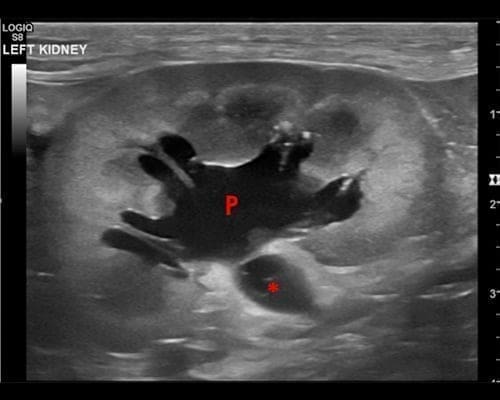

Ultrasonography of the Kidneys >>